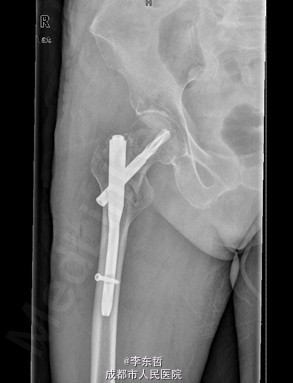

查体:T:37.2oC,P:72次/分,R:18次/分,BP:124/68mmHg。神志清楚,急性病容,皮肤巩膜无黄染,全身浅表淋巴结未见肿大。。颈静脉正常。心界正常,心律齐,各瓣膜区未闻及杂音。胸廓未见异常,双肺叩诊呈清音,双肺呼吸音清,未闻及干湿啰音及胸膜摩擦音。腹部外形正常,全腹柔软,无压痛及反跳痛,腹部未触及包块,肝脏肋下未触及,脾脏肋下未触及,双肾未触及。双下肢无水肿。 专科查体见:右髋关节局部肿胀,周围无红肿、皮肤损伤、溃疡和糜烂,右下肢短缩畸形,无表浅静脉曲张。右转子间轻触痛,扣痛。右髋活动受限,右下肢短缩畸形约5cm,轻度外旋、内收。右髋关节屈伸、外旋内旋、外展内收功能障碍。 X线片示:右股骨转子间骨折,累及大小转子,断端稍分离,未见明显错位,周围软组织肿胀明显,右髋关节在位。

初步诊断:1、右股骨转子间骨折(Evans III型);2、骨质疏松症。 诊疗计划:1、向患者及家属交待病情及注意事项。2、向上级医生汇报患者病情。3、完善术前相关检查。4、给予皮肤牵引、抬高患肢等对症处理。5、拟手术治疗。6、密切观察病情变化,根据病情及时处理。